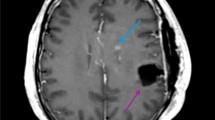

Illustration of the method used to quantify patient- and voxel-wise anomaly maps. (a) Based on a control group of 80 individuals, for each voxel a baseline cosine similarity between the voxel-wise connectivity patterns is calculated. Patient specific anomaly maps are generated by quantifying the connectivity profile deviation from the control group. (b) Illustration of the generated tumour tissue segmentations and a patient-specific anomaly map. Figure created with ITK-SNAP 3.8 (www.itksnap.org), MATLAB 2014a (www.mathworks.com) and Microsoft Office PowerPoint 2016 (www.microsoft.com).

Tumour recurrence coincided with functional anomaly before structural changes became apparent on structural imaging. (a) In Patient 01, regions of tumour recurrence at the third follow-up exhibited anomalous connectivity patterns already 2 months earlier at the second follow-up examination. Compared to all other voxels in the tumour vicinity, future tumour voxels were significantly more anomalous (p < 0.0001). (b) A detailed 3d illustration of the same patient showing the resection zone, tumour recurrence and overlap with the regions with aberrant connectivity profiles (anomaly z-score < − 1 for illustration). (c–e) In Patient 02, Patient 03 and Patient 04, regions of future tumour recurrence and progression showed a higher network anomaly compared to the structurally affected tumour vicinity (p < 0.0001). (f) In Patient 05, emerging tumour regions were mainly observed in the white matter and were not associated with significant preceding network anomaly (p = 0.1128). Figure created with ITK-SNAP 3.8 (www.itksnap.org), ParaView 5.5 (www.paraview.org), MATLAB 2014a (www.mathworks.com) and Microsoft Office PowerPoint 2016 (www.microsoft.com).